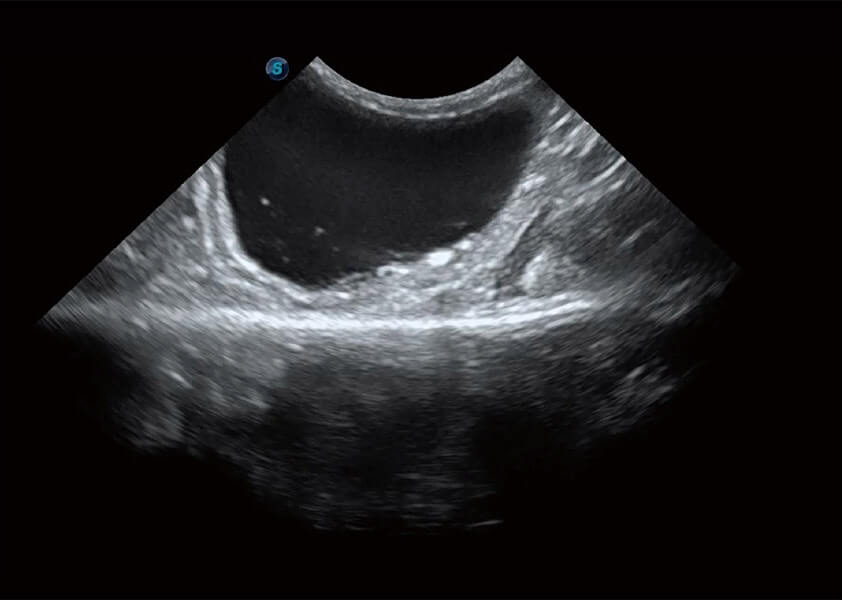

优异的基础图像

(犬)胆囊泥沙